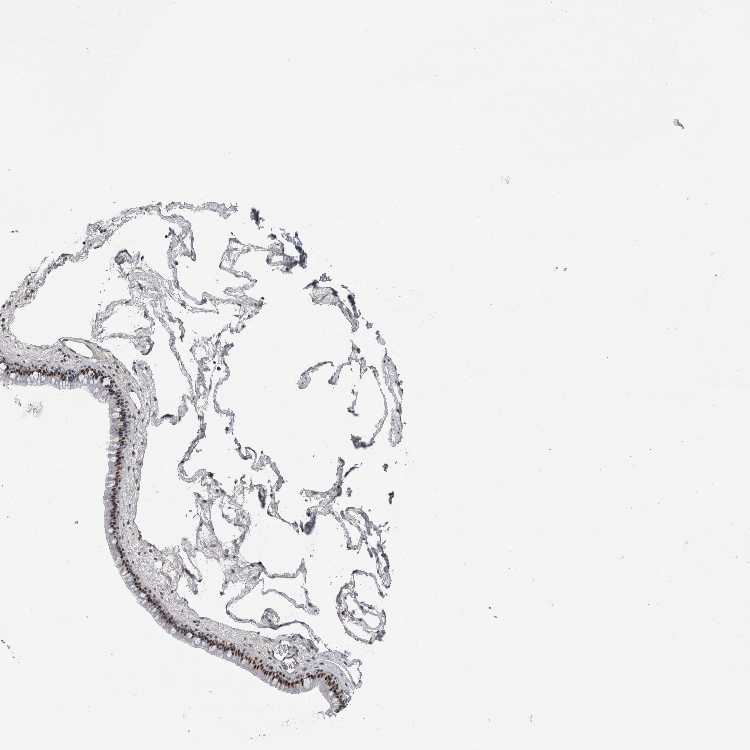

TISSUE PRIMARY DATA NASOPHARYNX Show tissue menu

NASOPHARYNX - Antibody stainingi

Antibody staining in the annotated cell types in the current human tissue is reported as not detected, low, medium, or high, based on conventional immunohistochemistry profiling in selected tissues. This score is based on the combination of the staining intensity and fraction of stained cells.

Each image is clickable and will lead to virtual microscopy that enables deeper exploration of all samples and also displays staining intensity scores, fraction scores and subcellular localization as well as patient and tissue information for each sample.

Antibody HPA026745

Basal cells Not detected

Ciliated cells (cell body) High

Ciliated cells (cilia axoneme) Not detected

Ciliated cells (ciliary rootlets) Not detected

Ciliated cells (tip of cilia) Not detected

Goblet cells High